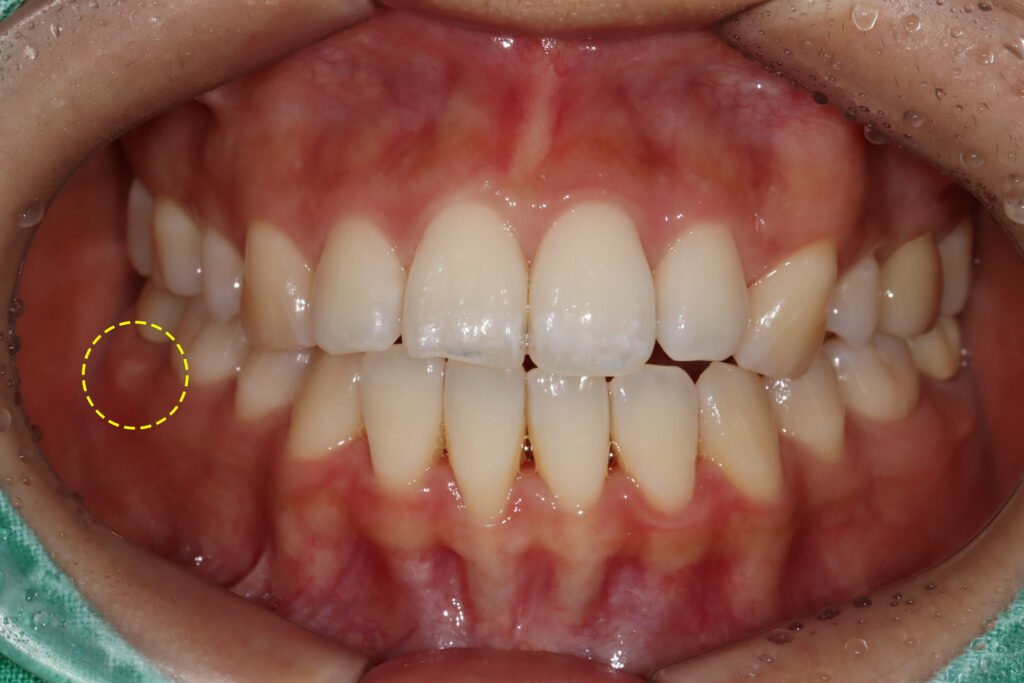

볼쪽으로 잇몸이 많이 부어 올라 있었고

치아의 흔들림도 있어 우선 재근관치료를

1달 후 부종이 사라지고 치근단 병소가

해소되어 최종보철물 제작을 진행하였습니다.

이후에도 점차 골소실이 메워져 수술 없이

마무리가 되었습니다.